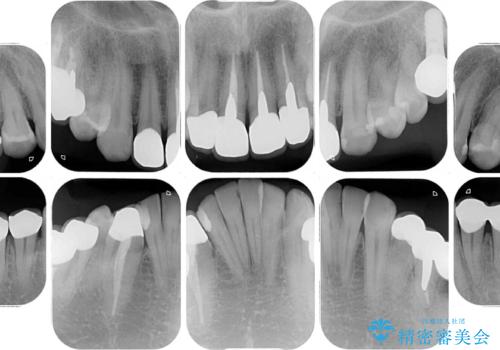

- 黄ばんだ前歯や目立つ奥歯の銀歯をきれいにしたいとのことで来院された患者様です。

欠損している歯や、割れてしまって抜歯の必要な歯などがあり、咬合力が強いため欠損部はインプラント補綴を前提に治療を行うこととしました。

しかしながら、左下の抜歯部位は骨欠損が著しく大きく、多大な垂直的骨造成を要するため、3歯を支台としたブリッジによる補綴治療とし、右下のみをインプラント補綴としました。

小さい修復物の銀歯が装着されている歯はセラミックインレーにて、その他はオールセラミッククラウンにて補綴治療を進めることとしました。